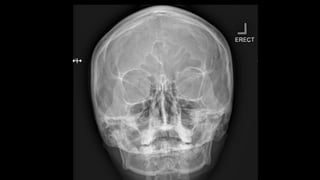

Occipitofrontal view

 This projection is used to demonstrate the frontal and

ethmoidal sinuses.

 It is also known as the Caldwell’s view.

 The patient is seated upright in front of the receptor and their

forehead and nose are placed against it.

 The beam is centred at around 15 to exit at the nasion.

⁰

• collimation

• lateral to the skin margins

• superior and inferior to the borders of the sinus cavities

Two frontal views of the skull demonstrate an incidental rounded, sclerotic lesion growing into the right frontal sinus (white arrows).

z Occipitofrontal view  Thisprojection is used to demonstrate the frontal and ethmoidal sinuses.  It is also known as the Caldwell’s view.  The patient is seated upright in front of the receptor and their forehead and nose are placed against it.  The beam is centred at around 15 to exit at the nasion. ⁰ • collimation • lateral to the skin margins • superior and inferior to the borders of the sinus cavities

Two frontal viewsof the skull demonstrate an incidental rounded, sclerotic lesion growing into the right frontal sinus (white arrows).